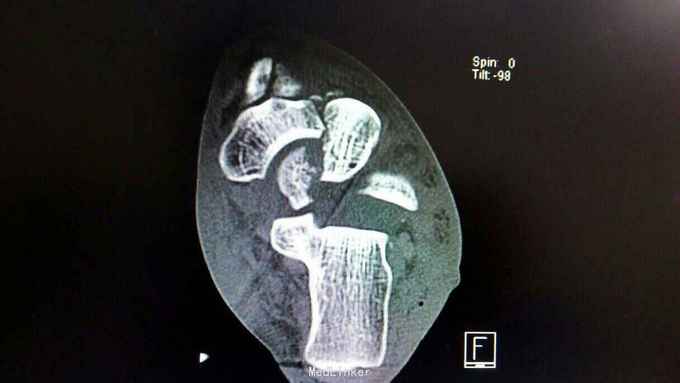

距骨骨折并脱位

骨折 距骨骨折

重物砸伤左足疼痛畸形14小时。

左踝至中足肿胀,左足内翻畸形,皮肤可见少许细小水泡,压痛,足背动脉搏动可,足趾活动可,感麻木。

距骨骨折并脱位 入院行闭合手法复位失败,予以跟骨牵引5天,石膏外固定3天,皮肤水泡、肿胀消退后行,距骨骨折脱位切开复位内固定+距舟关节融合。术后支具外固定,勿负重3个月。